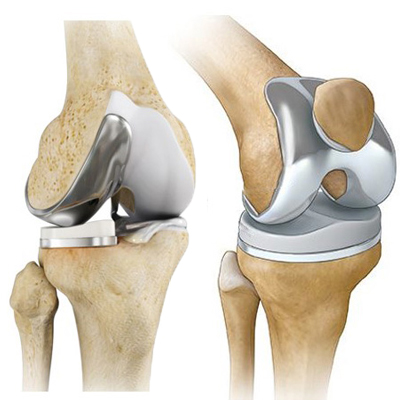

Knee arthroplasty, commonly called knee replacement surgery, replaces the damaged parts of the knee joint with high-quality artificial implants. It is ideal for patients suffering from severe arthritis, cartilage loss, deformity, chronic knee stiffness, or injury-related degeneration. This procedure helps restore smooth movement, reduce pain, correct alignment, and improve your overall quality of life.

HappyKnees is a trusted orthopedic center offering world-class knee replacement solutions. Dr. Akash Saraogi specializes in performing knee arthroplasty using modern techniques such as computer-assisted alignment, minimally invasive incisions, durable implants, and accelerated recovery pathways.